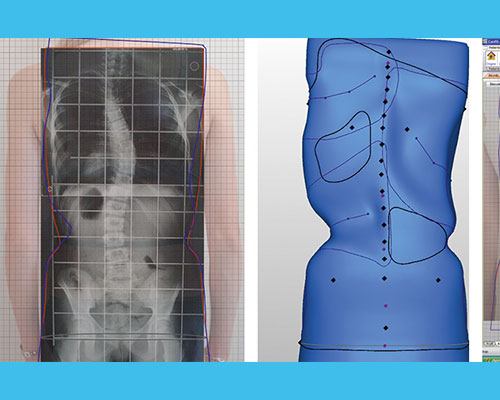

Positif (moulage) :

le moule positif est la reproduction originale du tronc du patient en 3D. Le positif sert pour le thermoformage de l’orthèse.